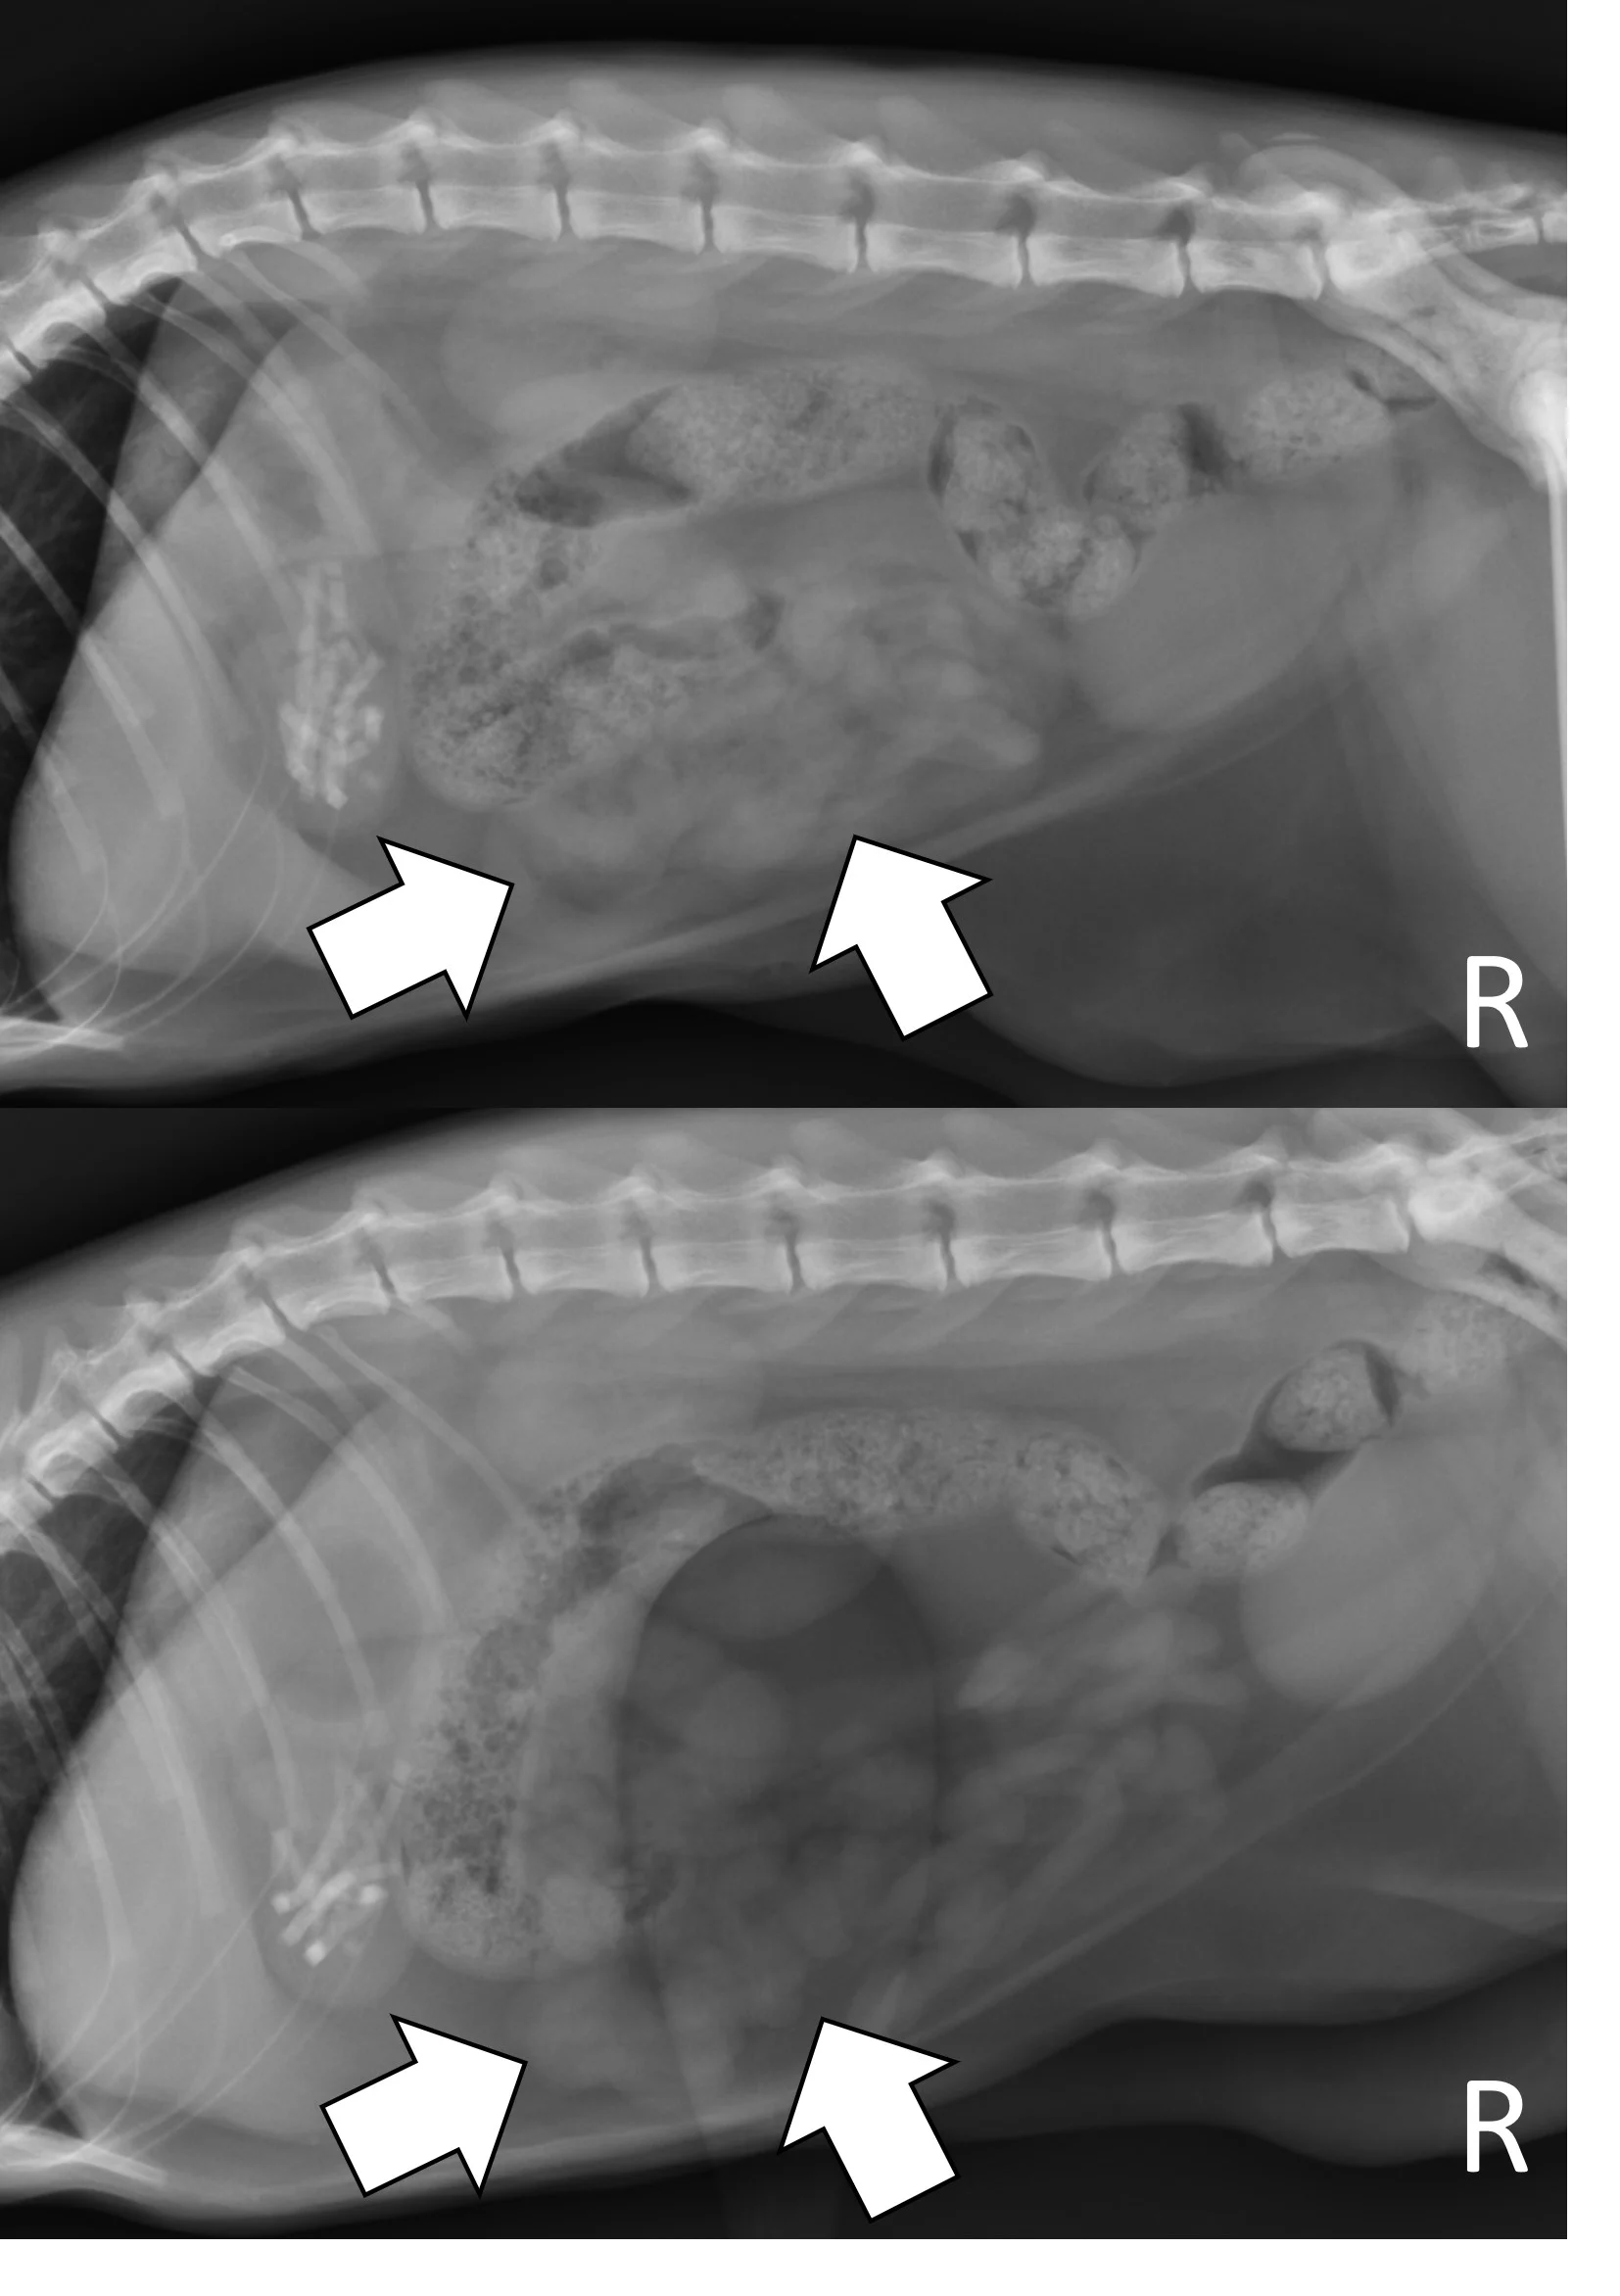

Pyloric Outflow Obstructions

Pyloric outflow obstructions occur when a foreign body lodges in the pyloric outflow tract or proximal duodenum and can cause variable gastric distention depending on the length of time the obstruction has occurred and whether the patient has recently vomited, as recent vomiting can reduce gastric size. Although exceptions are possible, acute complete obstructions typically cause mild to moderate gas dilation, and chronic partial obstructions can cause more moderate to severe dilation, predominately with fluid. A gravel sign, characterized by gravity-dependent mineralized ingesta often located in the pyloric antrum, is also possible with chronic partial obstructions (Figure 3).

Right lateral and ventrodorsal abdominal radiographs of a 2-year-old spayed Boston terrier with a chronic pyloric outflow obstruction secondary to a surgically confirmed foreign body in the proximal duodenum. The stomach is severely dilated, predominantly with fluid (pound signs). Mineral opaque material located ventrally is consistent with a gravel sign (arrow).

Modified Pneumogastrogram

A modified pneumogastrogram can be performed if there is insufficient gas in the stomach to fill the pylorus on the left lateral projection.12 A noncaffeinated carbonated beverage (60 mL; author reduces to 30 mL in patients <11 lb [5 kg]) should be given and a left lateral projection obtained immediately (Figure 8). The beverage may be administered free choice or via syringe if the patient is unwilling to drink. A modified pneumogastrogram produces less gas compared with traditional pneumogastrogram but is usually effective and avoids the need for placing an orogastric tube.

Left lateral radiographs of a 1-year-old spayed crossbreed dog with a pyloric outflow obstruction secondary to ingestion of part of a soft tissue opaque toy bone. On survey radiographs, there was insufficient gas in the stomach to fill the pylorus on the left lateral projection, masking the foreign body (top, arrow). A modified pneumogastrogram with a carbonated beverage was performed, resulting in the foreign body being outlined by gas and easily seen (bottom, arrow).